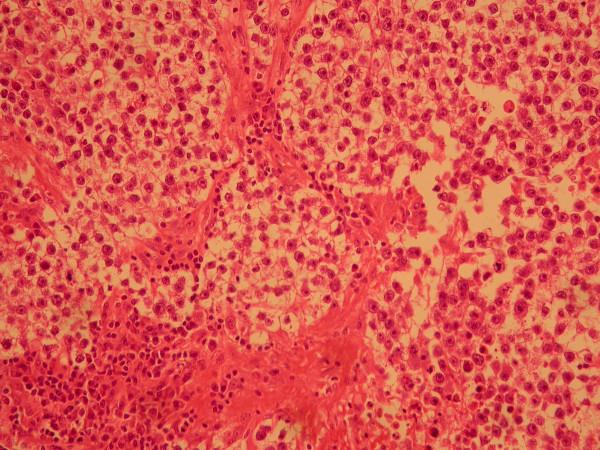

We present a case report of testicular seminoma in a 56 year old man with previously unreported histological findings. In this case seminoma tumour cells did not appear to have spread by the expected lymphatic route. There was no involvement of retro-peritoneal para-aortic lymph nodes. The tumour appeared to have spread directly along the vas deferans in the sub epithelial plane to the mesenteric lymph nodes.

我们报告一例56岁男性睾丸精原细胞瘤病例,具有此前未报道的组织学发现。在此病例中,精原细胞瘤肿瘤细胞似乎未按预期的淋巴途径扩散。腹膜后腹主动脉旁淋巴结未受累。肿瘤似乎是沿输精管在黏膜下层平面直接扩散至肠系膜淋巴结。

结论

这种类型的精原细胞瘤肿瘤扩散此前未被描述过,也不是精原细胞瘤公认的转移途径。在此病例中宏观临床表现为肿瘤标志物正常的I期肿瘤。然而,基于组织学和CT影像学检查结果,肿瘤的病理分期出人意料地升至III期。我们展示了这些不寻常的组织学发现。鉴于这一不寻常的组织学发现,我们强调准确分期以及在靠近腹股沟深环处切除精索的必要性。准确分期对于精原细胞瘤的治疗规划和随访至关重要,并决定预后。